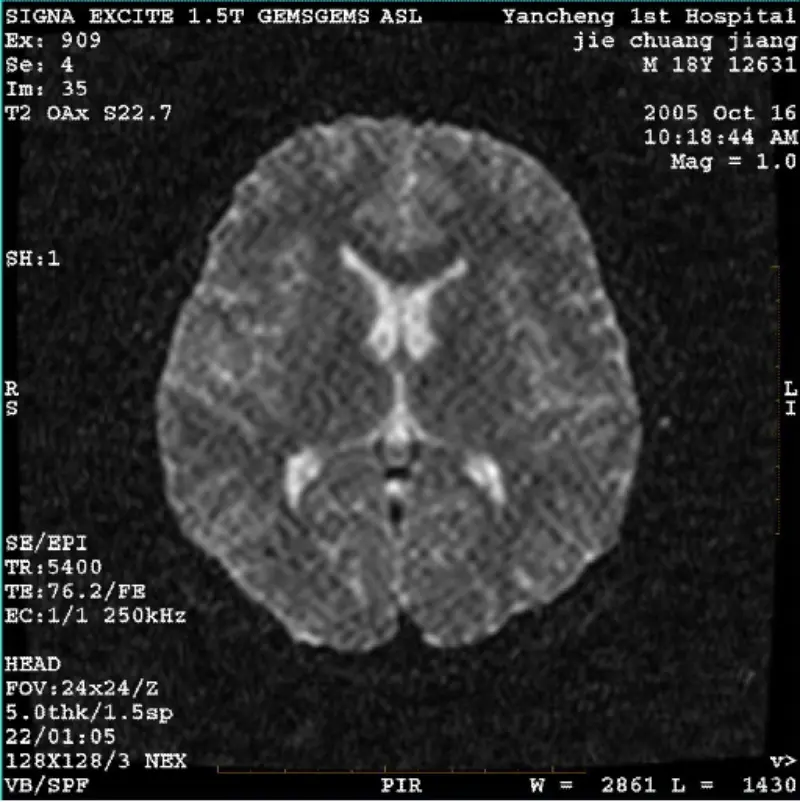

Irakurri gehiagoSISTEMA: 1.5T Signa Twin Excite II (Software Bertsioa 11.0M4) ARAZO/SINTOA DWI (zoom modua eta modu osoa) eta fiesta (zoom modua eta modu osoa) irudiak edukitzea erretikulatu edo panazko artifaktu ikusgaia, gorputzeko bobina edo burua erabiltzean bobina, beste errutinazko irudia normala dirud......